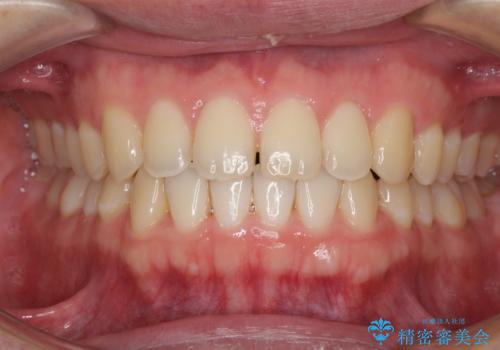

すきっ歯の改善 インビザライン矯正治療

インビザラインにより、上下の歯列を側方に拡大しつつ、前歯の隙間を閉じていくこととしました。

1日22時間の装着時間をしっかりと守ってくださったので、隙間がきれいに閉じ、口元の突出感も改善することができました。